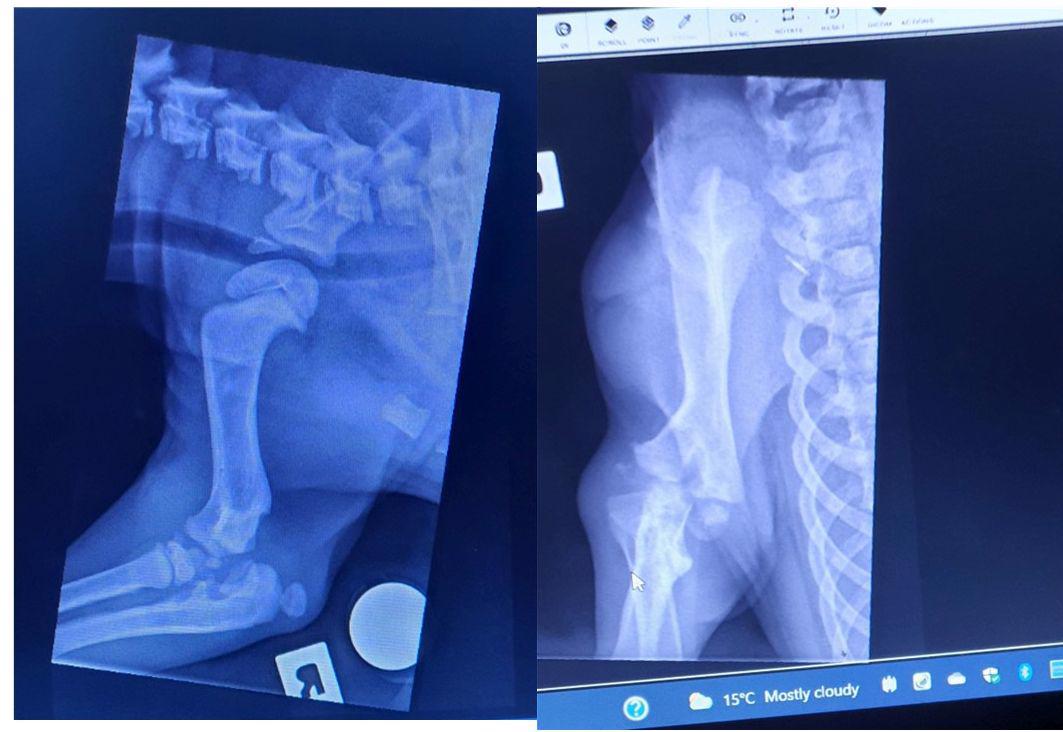

Update on puppy Simba with the broken leg.

We saw the specialist vet today for repeat xrays and consult to see if his bones had developed enough to give clear views this time as CT and previous xray done 2 weeks ago where inconclusive. Xrays taken today were much more informative but unfortunately worse than anticipated. His little joint is literally smashed beyond repair - see xrays attached. The specialist said it looks like the bone has detached then those pieces figuratively stomped on to cause a mushy mess and is totally irrepairable. Only option to save his life is a full limb amputation. This has been scheduled for tomorrow morning. Being so young he will quickly adapt to three legs, will be important to keep him on the lean side. Estimate for this surgery is between 3-4 thousand. Our fundraising so far has given quite a bit towards this but please share his Give a Little page so we can raise the rest. To say I am devastated it has come to this is beyond words and how the heck he managed so well is beyond even the specialist's thoughts. We did ask if this was a Super Vet job and unbelievably this guy worked for 5 years under Noel Fitzpatrick and said that even he would not be able to reconstruct this joint. Good news is that Simba is now 7.7kg, nearly doubling his weight in 2 weeks.